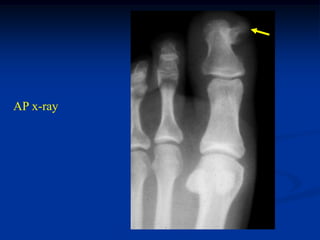

31 year female with enchondroma great toe